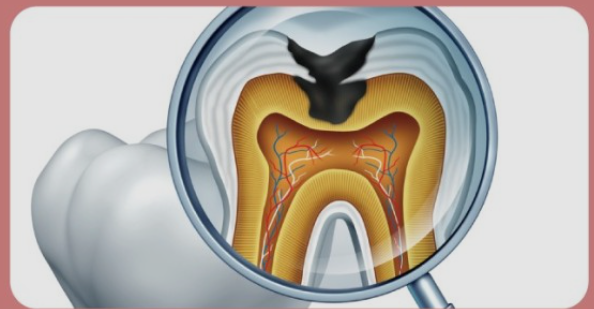

치아 신경치료란?

외상 또는 충치로 인해 치아의 치수(신경)가 손상되었거나 염증이 생기게되면 통증이 느껴지게 되요. 문제가 생긴 신경을 방치하게 되면 일상생활에 지장이 있을 정도로 통증이 심해지며 염증이 점점 커지기 때문에 손상되었거나 염증이 생긴 치수를 제거하는 것이 치아 신경치료이에요.

신경치료 후 보철치료를 통해 약해진 치아를 보존하는 치료까지가 치아 신경치료가 마무리 되었다라고 볼 수 있어요. 이유는 치수의 역할이 중단되어 치아가 약한 상태가 되고 쉽게 부러지거나 쪼개질 수 있기 때문이에요. 치수는 우리 치아에 영양과 수분을 공급해주는 역할을 하는데요, 이러한 신경조직을 전부 제거하게 되면 치아는 더이상 영양과 수분을 공급받을 수 없는 상태가 되고 시간이 지날수록 마른 나뭇가지처럼 약한 상태로 변하게 되요. 약해진 치아를 오래 사용하려면 크라운을 씌워 치아를 보호해 줘야 하기 때문에 신경치료 후 크라운은 반드시 필요한 치료 과정이에요.